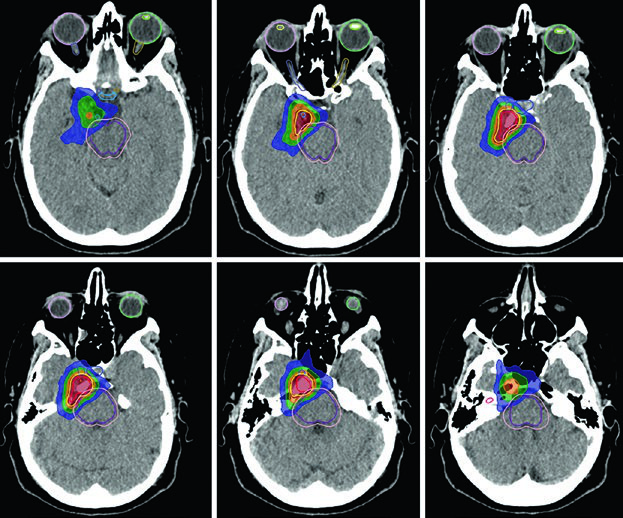

O caso da Figura 29.9 ilustra um schwannoma vestibular direito no ângulo cerebelopontino que comprime o pedúnculo cerebelar médio e a ponte, estendendo-se para o fundo do canal auditivo interno. Há compressão do tronco encefálico e do nervo trigêmeo cisternal, com apagamento parcial moderado do quarto ventrículo. Na Figura 29.10, o tratamento de um schwannoma do APC esquerdo com SRS a 12,5 Gy de prescrição mostra a isodose de prescrição cobrindo o tumor, com isodose de 20 Gy no centro e 5 Gy na periferia, preservando tronco encefálico e cóclea como OARs.